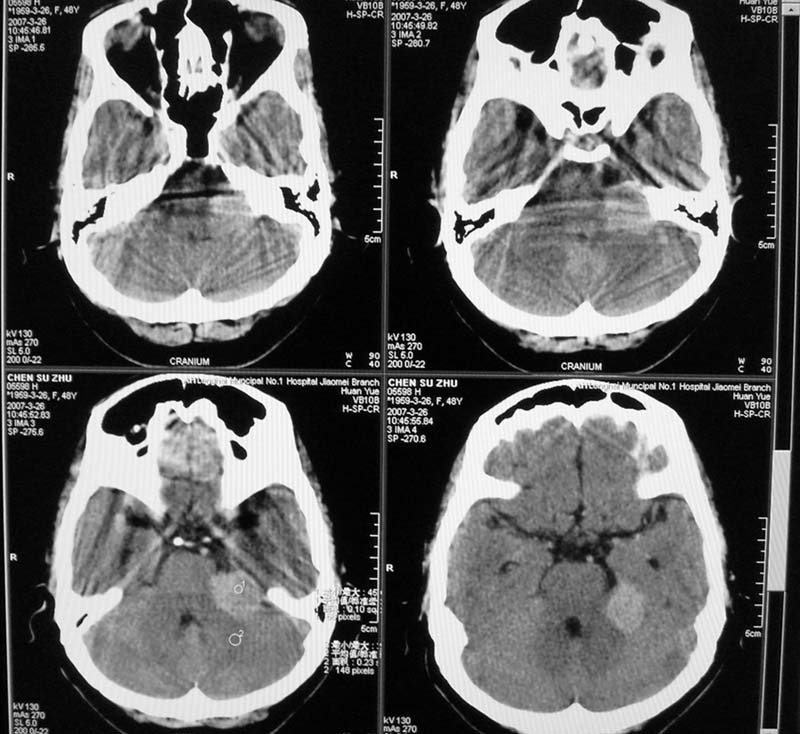

标题: CT8208:女,48岁,反复头晕半年余,无听力、视力障碍 [打印本页]

患者,女,48岁,反复头晕半年余,无听力、视力障碍。病人已手术,结果明天传。

1.病灶形态规则,密度略高,边界尚清,周围无水肿带,无明显占位效应

2.病人应已强化扫描

3.首先考虑动脉瘤,其次考虑脑膜瘤

左侧岩骨局部受压,考虑脑膜瘤可能性大

内听道没有加层薄扫,显示不太清,所以鉴别听神经瘤和脑膜瘤困难.左额叶低密度是梗塞?

左侧桥小脑角区高密度肿块,周围无水肿及明显占位效应,岩骨尖受压吸收,内听道未见扩大,无听力异常,右侧颅骨外板高密度影,边缘锐利,考虑:左侧脑膜瘤,右侧颅骨骨瘤。左侧岩骨尖有破坏,三叉神经瘤待排。

结果:脑膜瘤,谢谢。